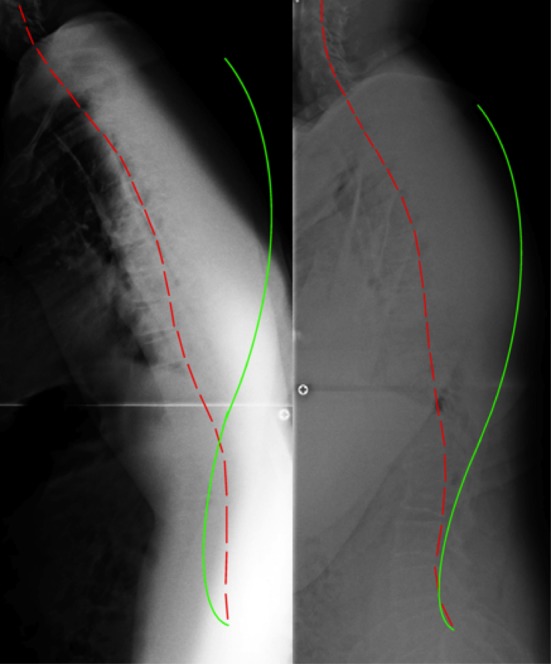

The lateral full-spine radiograph (Figure 2) demonstrated a significant forward lean, as the measurement from the horizontal distance from the posterior-superior vertebral body corner of T1 to the posterior inferior body corner of S1 measured 192.3 mm (ideal=0 mm. [10] The lateral cervical specific image (Figure 3) demonstrated a forward head position of 67.5 mm (normal=0–15 mm [11]), an ARA from C2–C7 of –29.6° (normal= –31° to 42° [11–13]), and an atlas plane angle of –7.6° (normal= –29° [11, 12]). The AP cervico-thoracic view (Figure 4) showed a large right head translation (62.7 mm; normal=0 mm [10]), with a cervico-dorsal angle of –4.8° (normal=0° [10]) and an Rz angle of 15.6° (normal=0° [10]). The AP lumbar view (Figure 5) showed a right thoracic translation (–12.6 mm; normal=0 mm [10]), with unleveling of the pelvis lower on the right.

The patient’s posture as seen visually (Figure 1) improved dramatically. Follow-up radiographic assessment confirmed and quantified the significant improvements in the patient’s posture (Figures. 3–6).

The total body forward shift from T1-S1 reduced (132 mm vs. 192 mm),

forward head posture reduced (36.5 mm vs. 67.5mm),

there was an increased cervical lordosis (–37.2° vs. –29.6°),

an increased atlas plane angle (–19.8° vs. –7.6°),